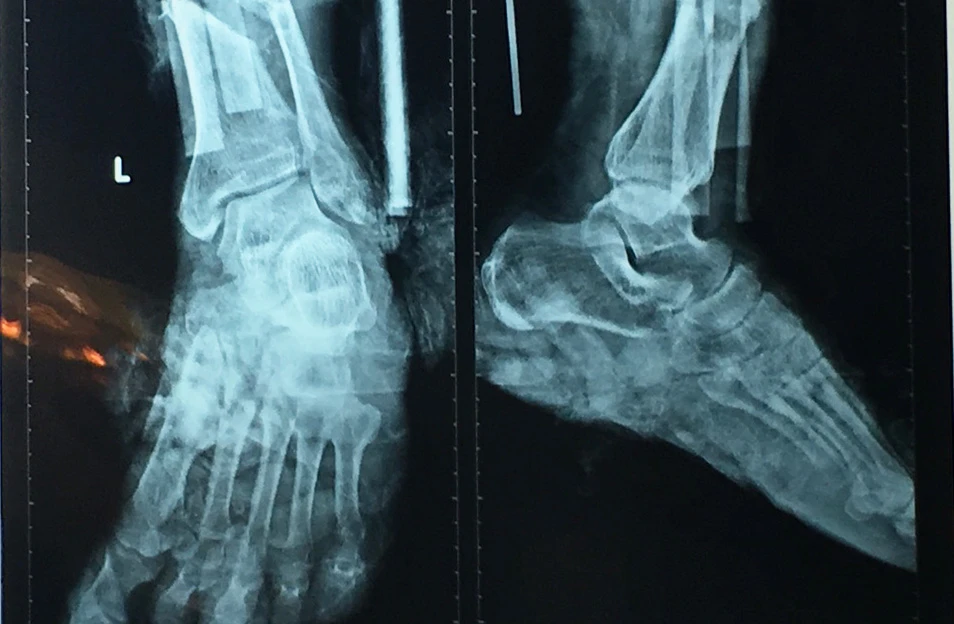

Kết quả chụp X quang cho thấy ông T bị đứt gần lìa 1/3 dưới cẳng chân trái. Ảnh: HÒA KHÁNH